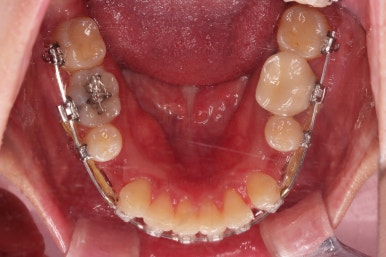

초진 시 입안의 모습입니다.

전반적으로 치열이 삐뚤고, 특정 앞니는 톡 튀어나가 미적으로 좋지 못한 상황이었습니다.

이갈이, 이악물기 습관도 있어서 앞니는 삐뚤어진 채로 치아가 많이 갈려있는 상황이었습니다.